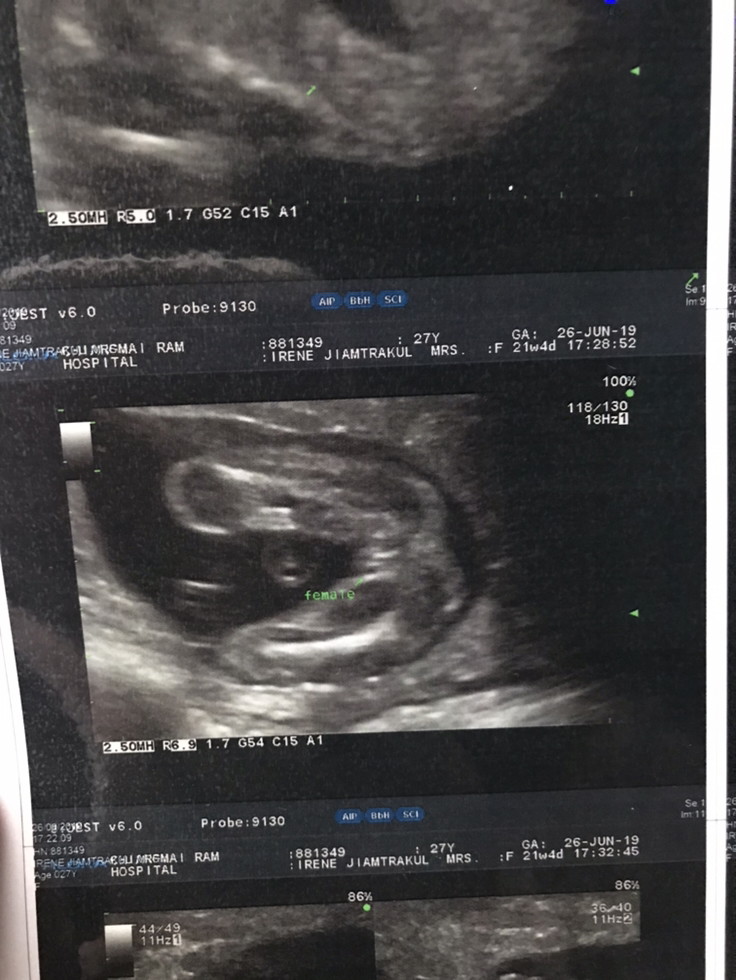

ผญ ค่ะ เห็นตอน 22 วีคค่ะ☺️